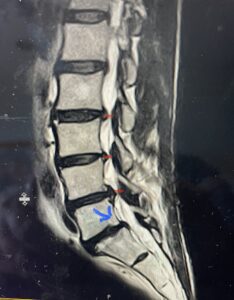

(Fig. 2) T2-weighted lumbar MRI demonstrating severe lumbar stenosis (red markers) and a grade 1 spondylolisthesis at L5-S1 (blue arrow)

This 59 year-old female had severe bilateral leg pain and numbness over a 6-month period. The patient had failed conservative treatment with physical therapy, chiropractic care, and medications. MRI revealed that she had severe lumbar stenosis with a grade 1 spondylolisthesis or “slipped disc” at L5-S1 (Fig. 2). In addition, she had previously undergone both front and back surgery for severe cervical stenosis where her posterior hardware had failed because of her severe osteoporosis requiring us to remove the posterior hardware. This required her to have an anterior or front operation which allowed better fixation to her spine because of the load-sharing nature of the interbody grafts in addition to her anterior cervical plate (Fig. 3).